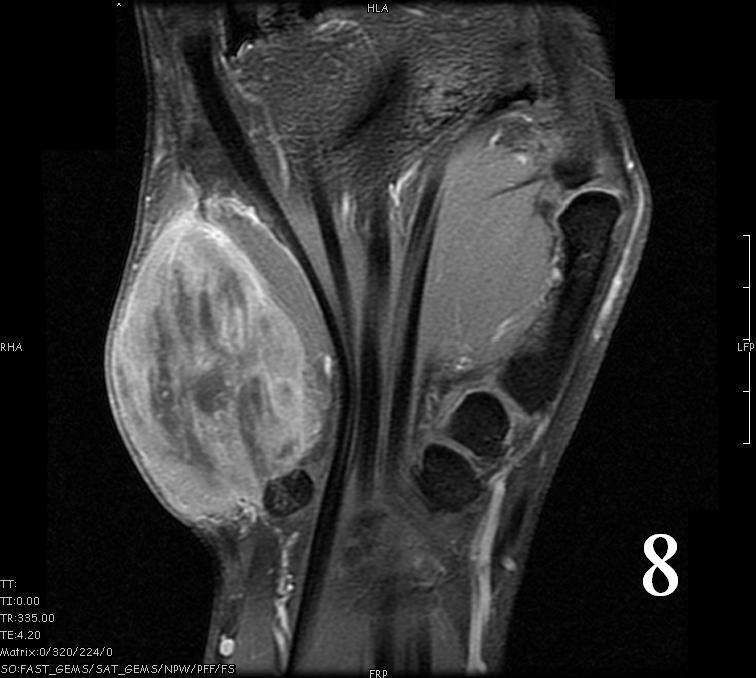

MRI

- Heterogeneous mass (does not follow signal of skeletal muscle)

- Isointense to skeletal muscle on T1 (Fig. 4, Fig. 5, Fig. 7, Fig. 8)

- Hyperintense signal on T2, sometimes low to intermediate signal on T2 if there is extensive fibrous tissue within the tumor (Fig. 6, Fig. 9).

- Prominent vascularity

- Deep enhancement with gadolinium

- Possible extensive hypercellular fibrous tissue and hemosiderin seen on T2

Fig. 4-9: MRI of a rhabdomyosarcoma of the hand. The MRI is nonspecific and shows a heterogeneous mass particularly on postgadolinium images T1 W images (Fig. 8) and T2 W images (Fig. 9).